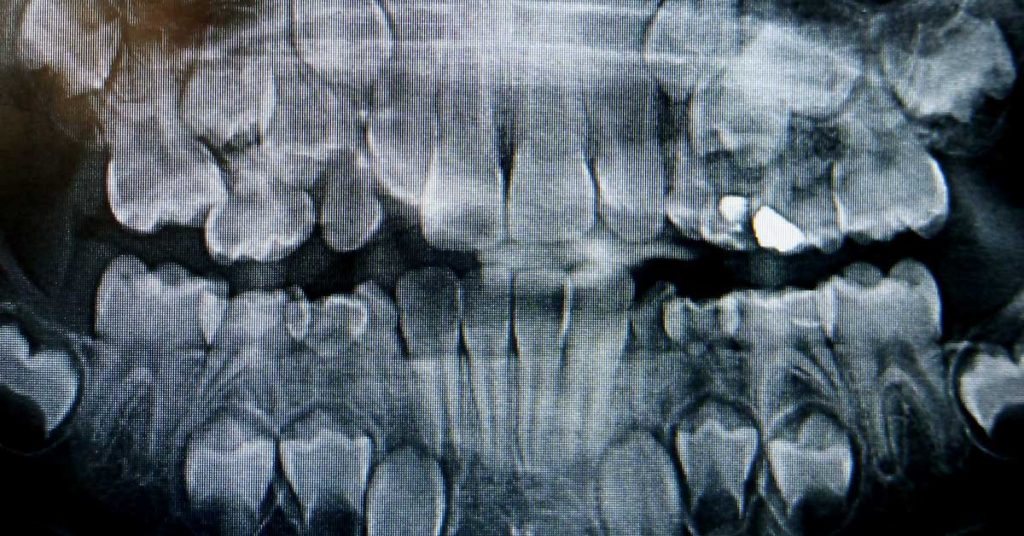

Sometimes there are incredible stories woth retelling, and this is one of them. What started with jaw pain, ended with the removal of 526 teeth for a 7-year old boy from India. In August 2019, he was admitted to a hospital in the southern city of Chennai, India, due to the swelling and pain near...